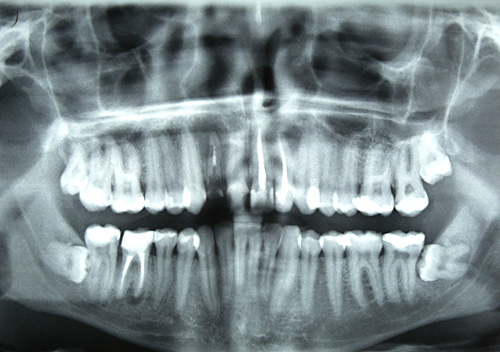

Теперь для прогнозирования переломов можно использовать зубной рентген, который сделал врач стоматолог во время очередного приема, уверяют ученые из Академии Салгренска. Результаты исследования опубликованы в издании Nature Reviews Endocrinology.

В предыдущем исследовании ученые из университета Гетеборга показали, что редкая костная структура трабекулярной кости нижней челюсти связана с высоко вероятностью переломов в будущем.

Ученые провели дальнейшие исследования и выяснили, что зубные рентгены можно использовать для исследования структуры кости нижней челюсти, чтобы спрогнозировать риск переломов в будущем. С помощью зубного рентгена каждый сможет предугадать понадобится ли ему в будущем рентген на дому в Санкт-Петербурге при получении травмы.

«Мы установили, что разреженная костная структура в нижней челюсти в средние годы непосредственно связана с риском переломов в других частях тела позже в жизни», сказал Лорен Лисснер из медицинского института Академии Салгренска.

Чем старше пациент, тем более сильна связь между редкой структурой челюстной кости и переломами других частей тела.